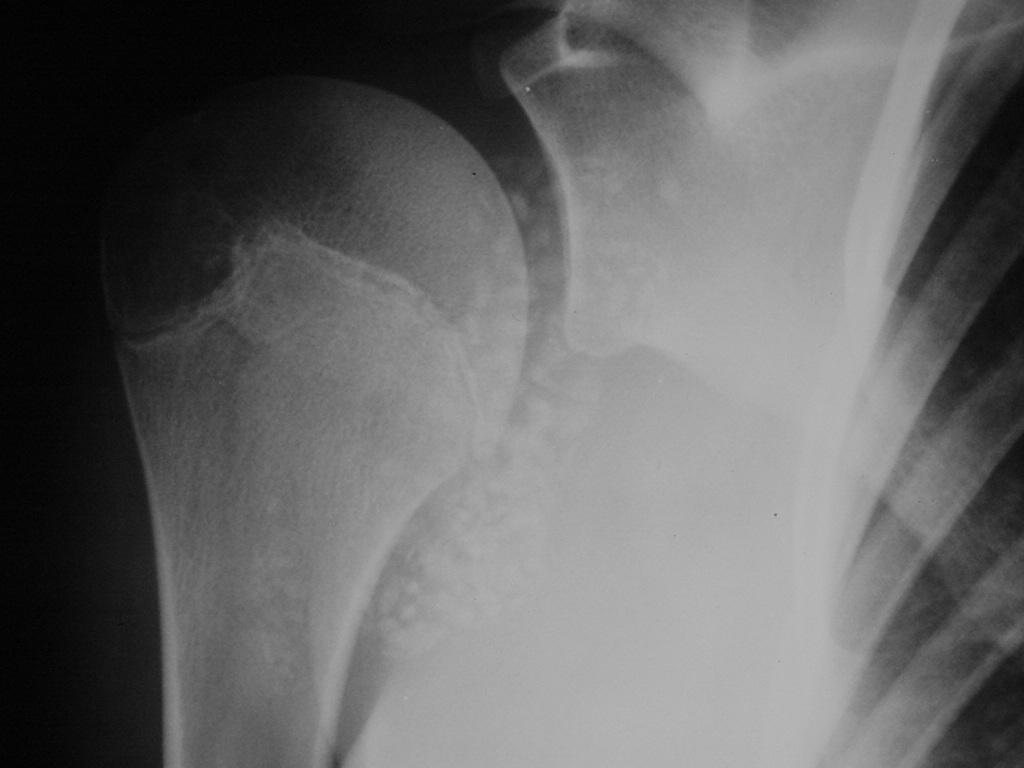

Synovial chondromatosis is an uncommon, benign, process that occurs in large joints, such as the knee (50%), hip, elbow, or shoulder. This process mainly affects synovium and hence most commonly arises from joints and tendons which are lined by synovium. Synovial Chondromatosis may also affect bursae and extend into surrounding soft tissues. This condition is seen in patients between 20 and 50 years of age and most commonly in men (male-female ratio of 2-4/1). The patient usually complains of pain, stiffness, crepitance, swelling, and joint locking. The knee is the most common site to be affected. Symptoms are long-standing and progressive. The plain x-ray may be normal (5 to 33%) or there may be small flecks of calcification (Fig. 1 & 2). On MRI the nodules of cartilage are easily seen. MR imaging may also show synovial thickening, joint erosions and intraarticular calcifications. The signal characteristics of these intraarticular bodies depend of their composition. If mineralization is not present the signal intensity follows the cartilage signal with intermediate signal on T1 images and high signal on T2 weighted MR images. Uniformly calcified bodies follows bone density on all sequences with bone marrow signal centrally and low signal peripherally (Fig. 3-5). Histologically the cartilage is arranged in nodules, which are quite cellular (Fig. 7-9). Synovial lining is present surrounding the cartilage nodules (Fig. 8). The cartilage nodules are often referred to as loose bodies however they are not really loose and embedded in the synovium lining. This is considered a metaplastic condition as opposed to a true neoplastic condition. Rarely it may turn into a malignancy usually a low grade chondrosarcoma. Malignant change is suggested by deep erosions into adjacent bone.

Fig. 1 & 2. Plain X rays of right shoulder synovial chondromatosis. AP (Fig. 1) and outlet (Fig. 2) views demonstrate multiple calcified bodies. Joint erosions are not seen on these x rays.